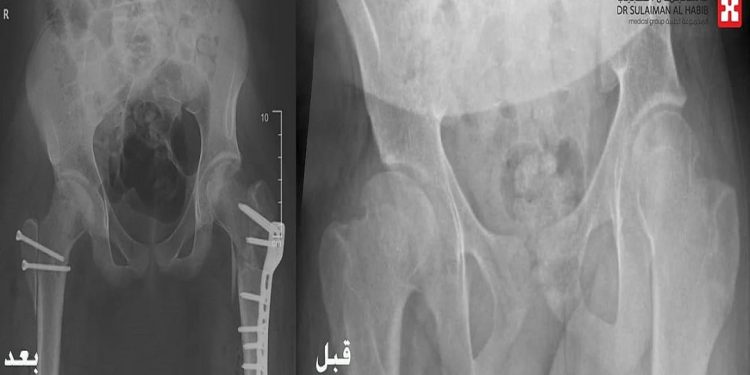

وأشار الدكتور الرفاعي إلى أن الفريق الطبي أجرى مجموعة من الفحوصات الدقيقة باستخدام الرنين المغناطيسي والتصوير المقطعي والأشعة السينية الرقمية، والتي كشفت عن وجود ميلان حاد في الحوض، وقصور حركي في مفصل الوركين، بالإضافة إلى اختلاف في طول الفخذين.

واستغرقت العملية الجراحية نحو 5 ساعات تحت التخدير العام، حيث أُجري خلالها خلع جراحي لمفصل الورك باستخدام تقنية جراحية متقدمة تُعرف باسم (Modified DUNN Procedure)، تلاها عزل الشرايين المغذية لرأس عنق الفخذ الأيسر، وتطويل نسبي لعنق الفخذ، مع ترميم كامل لمفصلي الورك، وإعادة استقامة عظام الحوض.